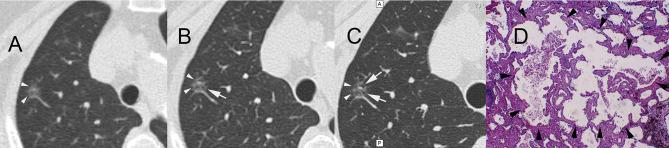

A total of 113 patients with pulmonary nodules were screened using LDCT. For nodules with the largest diameters, an HRCT local-target scanning program (combined scanning scheme) and a conventional-dose CT scanning scheme were also performed. Lung nodules were subjectively assessed for image signs and compared by size and malignancy rate measured by AI-assisted software. The nodules were divided into improved visibility and identical visibility groups based on differences in the number of signs identified through the two schemes.

The nodule volume and malignancy probability for subsolid nodules significantly differed between the improved and identical visibility groups. For the combined scanning protocol, we observed significant between-group differences in subsolid nodule malignancy rates.

使用LDCT对113例肺结节患者进行筛查。对于最大直径的结节,还执行了HRCT局部靶扫描程序(联合扫描方案)和常规剂量CT扫描方案。对肺结节的图像征象进行主观评估,并通过AI辅助软件测量的大小和恶性率进行比较。根据两种方案识别出的征象数量差异,将结节分为可见性改善组和可见性相同组。

实性结节的结节体积和恶性概率在可见性改善组和可见性相同组之间存在显著差异。对于联合扫描方案,我们观察到实性结节恶性率在组间存在显著差异。